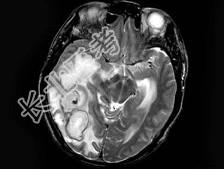

- 单项选择题男,47岁, 发热、头痛、呕吐1周,MRI检查, 最可能的诊断是 ( )

A、脑转移瘤

B、脑脓肿

C、胶质瘤

D、血吸虫性脑病

E、未见异常